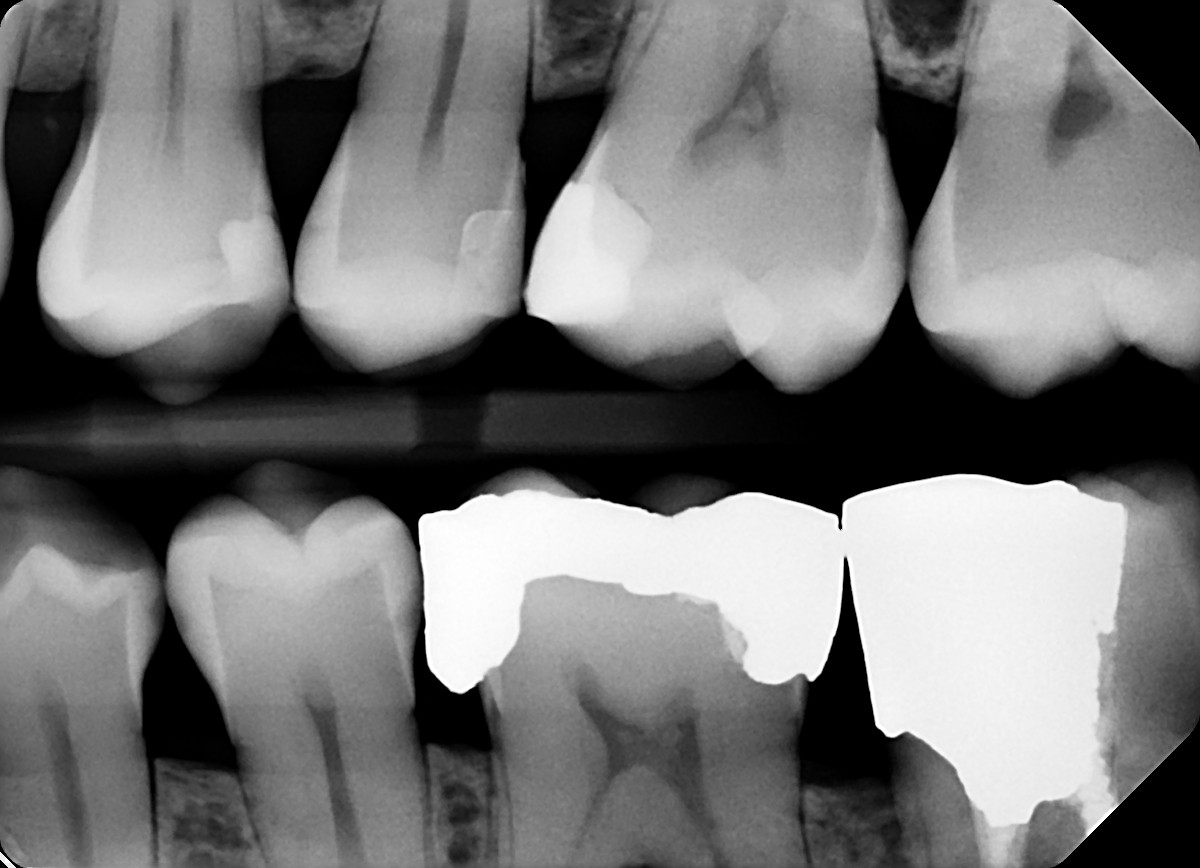

1.  In the X ray bellow for which jaw periodontal bone loss is evident?